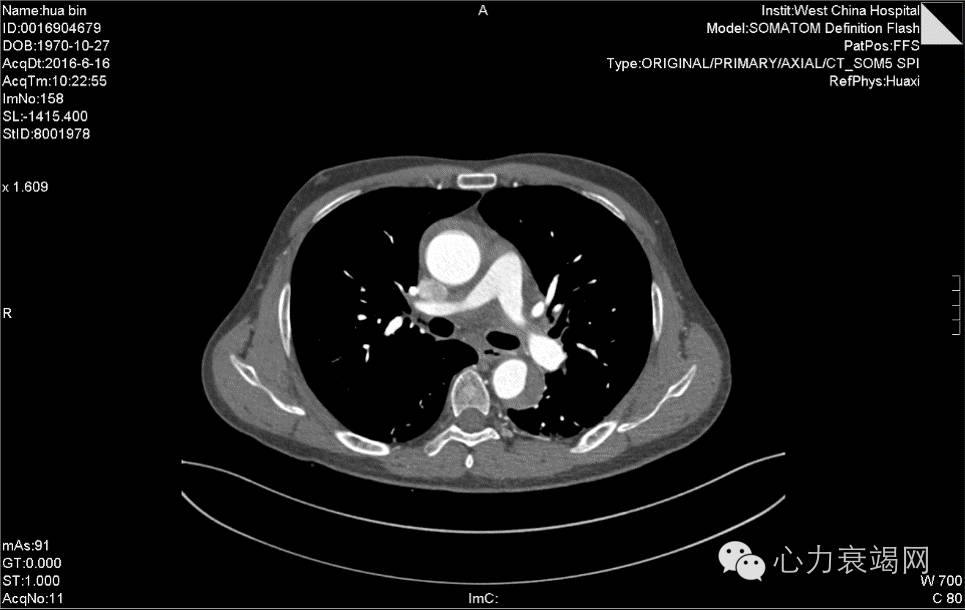

夹层动脉瘤CT

CTA示:主动脉壁内血肿,起自升主动脉根部,至降主动脉下段,并累及头臂干、左颈总动脉、左锁骨下动脉起始处,主动脉弓水平壁内血肿内见团片状低密度影,并见内膜小破口,增强见造影剂由破口进入壁内血肿,考虑局限性夹层?或其他,请结合临床。脾动脉稍迂曲。心脏稍增大,心包少许积液或心包增厚,主动脉壁少许钙化。双肺少许炎症,下叶为主。双侧胸腔少许积液或胸膜增厚。肝左外叶小囊肿。肝右后叶钙化灶。左肾囊肿。